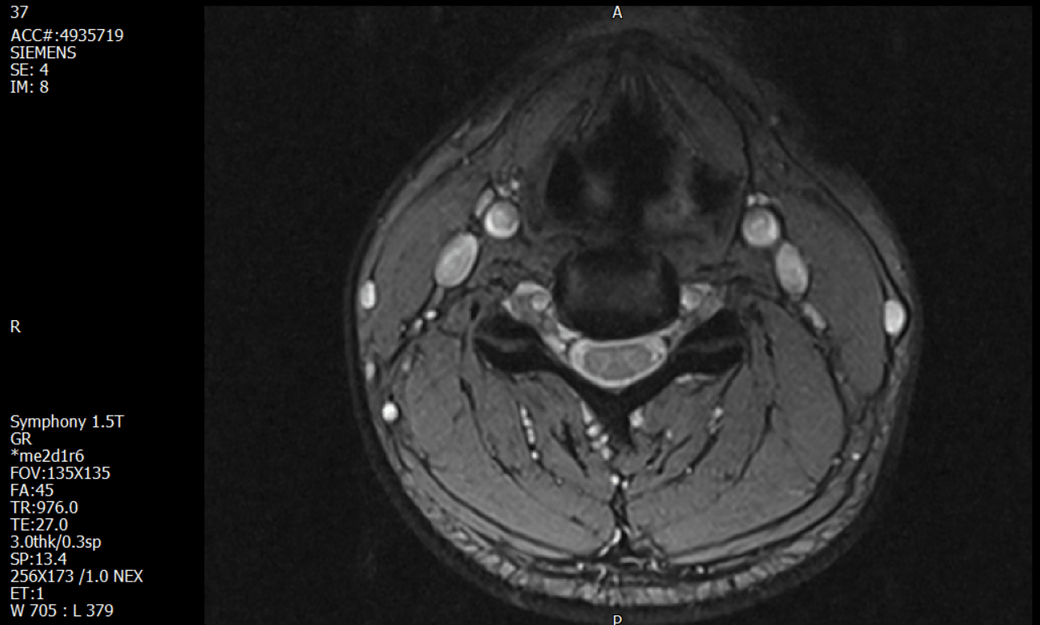

경추 요추 디스크 MRI판독 부탁드립니다.

- 3개월전 좌측 상지 저림(힘빠짐) 발생. 이틀뒤 에 좌측 하지 저림(힘빠짐) 발생.

(힘이 축처지는 느낌이라서 힘빠짐이라고 하지만, 실제 근력 문제, 감각이상, 활동 문제 없음)

-11월, 증상발생 직후 잠실소재 척추전문병원 MRI 요추경추 촬영 후 신경외과 박사 진료, 허리는 매우 건강, 경추는 퇴행성 진행되고 있지만 디스크라고 보기 어려움. 신경막만 살짝 건드리는 정도고 이 정도로 힘빠짐이나 저림이 오지 않고 원인은 다른 곳에 있을 가능성.

-12월, 분당서울대병원 재활의학과 진료, MRI 영상보고 딱히 다른 말은 없었음. 근전도 검사해보자 해서 신경전도, 근전도 검사 진행, 검사결과 이상없었고, 신경쪽 문제는 아예 배제해도 될것이라고 함. 정신쪽에 기인한 문제일 가능성 제시.

-올해 1월, 국립암센터 재활의학과 진료, 병명을 찾기가 쉽지 않을 것

-올해 1월, 분당서울대병원 신경과 진료, MRI영상보더니 디스크가 있고 저림과 힘빠짐이 이에 기인했을 가능성이 충분히 있다고함. (경추만 말한것인지 요추도 포함인지 모르겠으나 디스크 시술 방안을 제시함) , 팔다리가 우연이 동시에 저림이 올수 있는지에 대해서 물었더니 이틀 상간으로 발생했기 때문에 동시라고 보기 어렵다고함...

1. MRI 상 , 경추와 요추에 디스크가 있나요? 있다면 좌측 팔과 다리에 저림 및 힘빠짐을 줄 정도인가요?

• 1. MRI 사진을 보았을 때 디스크를 의심해볼 수 있는 소견이 살짝살짝 보이긴 합니다만, 상하지의 저림 및 힘빠짐을 유발할 정도인지는 솔직히 회의적입니다.

2. 영상의 퀄리티는 나쁘지 않아 보입니다. 굳이 재촬영을 하실 필요는 없어 보입니다.

3. 개인적으로는 디스크로 인한 증상이 아닐 것으로 보나, 만약 디스크가 맞다면 우연하게 목과 허리 디스크 발병이 이틀 간격을 두고 나타났을 가능성을 생각해야 하는데, 현실적으로 그 가능성이 높지 않습니다.

4. 말씀하신 것처럼 특히 요추부 MRI는 디스크를 찾기 어렵습니다.

상기 MRI 소견으로는 심한 증상을 보일 정도는 아니며 디스크의 가능성은 적어보입니다.